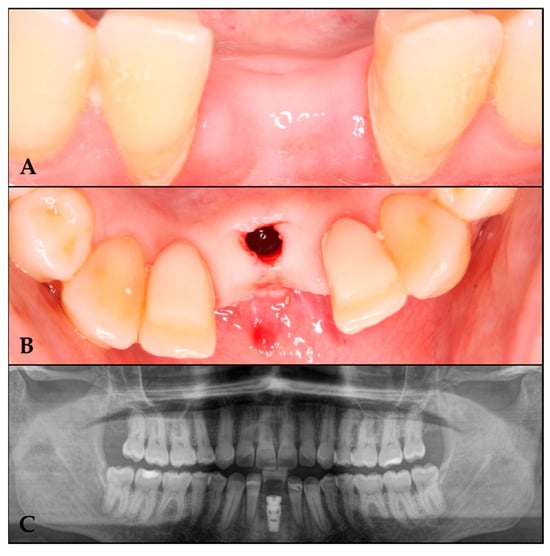

A six-month follow-up period was conducted prior to the placement of the barrier. Anesthesia was administered, the screws were removed, and the barrier was sectioned into two segments for extraction (Figure 4).

Figure 4. Barrier removal. (A) Lifting of the cover. (B) Area irrigated with physiological saline solution. (C) Barrier section. (D) Regenerated area.

Following a four-month healing period, implant placement was initiated under local anesthesia. A computer-guided surgical stent was utilized to achieve optimal prosthetic positioning. A bone core sample was then harvested using a trephine drill for histological analysis.

Osteotomy preparation was performed according to the planned implant dimensions (Figure 5), followed by placement of a C1 MISS implant (3.75 mm diameter × 10 mm length) in the prosthetically driven position to fulfill restorative requirements.

Figure 5. Implant placement in the regenerated area. (A) Regenerated area at 10 months. (B) Implant in the regenerated area. (C) Orthopantomography with the implant in the regenerated area.